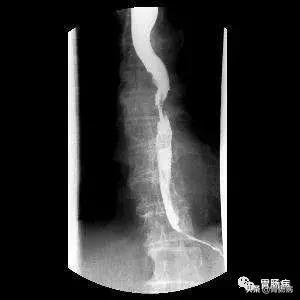

1、X线钡餐检查,也叫食管片。优点是简便,准确性高,病人痛苦少,不但可观察食管病灶部位,长度,梗阻程度,溃疡大小与深度,有无穿孔和瘘管形成,而且可观察食管粘膜和食管动力学改变。